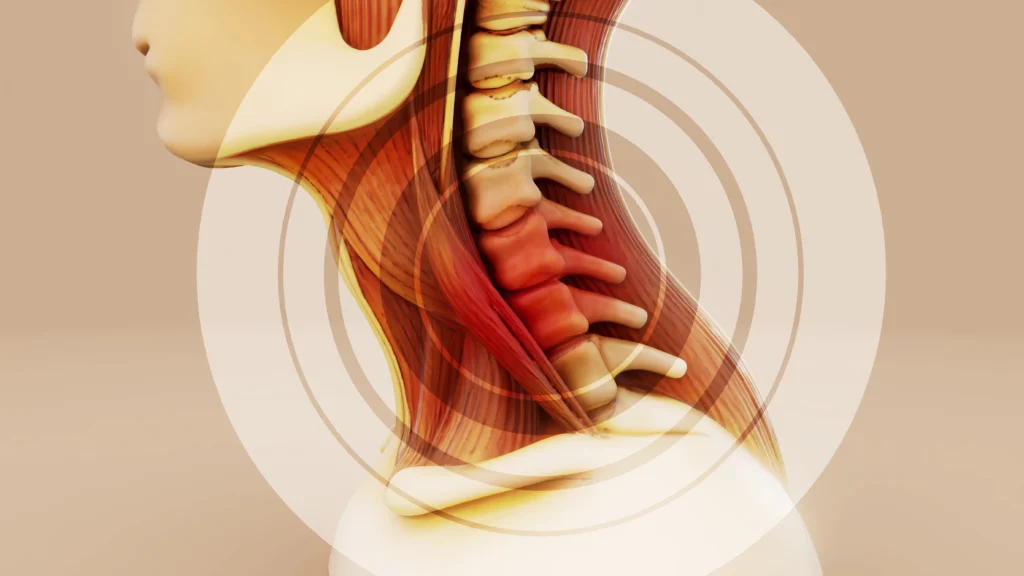

Telefon Kullanımı Boyun Sağlığını Nasıl Etkiler?

Boyun Fıtığı Masajı Nedir ve Faydaları Nelerdir?

Telefon Kullanımı Boyun Sağlığını Nasıl Etkiler?

Boyun Fıtığı Masajı Nedir ve Faydaları Nelerdir?